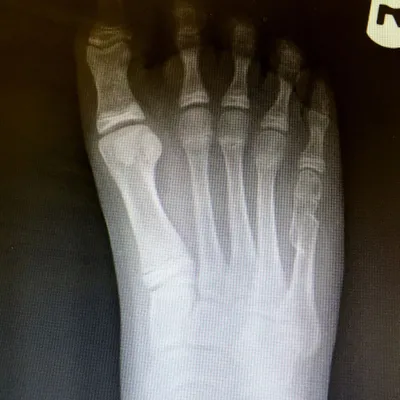

Examples of Pediatric Foot Fractures (Below)

Pediatric Metatarsal Neck Fractures

Pediatric Coalition Fracture of the DIPJ fifth toe initial and healed